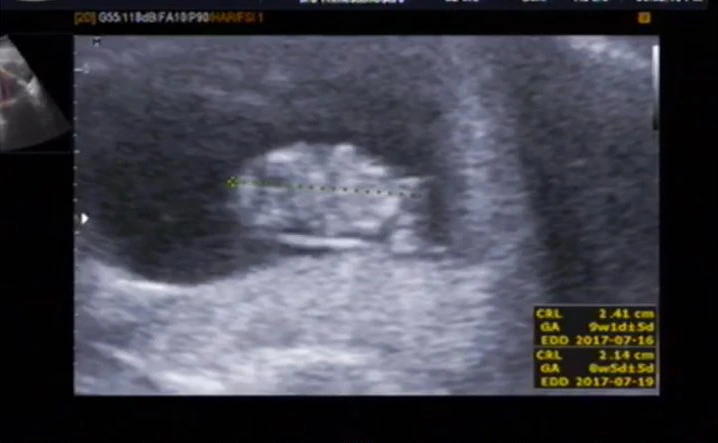

모든 아이는 이 작은 점에서 시작한다. 애기 집만 보이다가 어느 순간이 되면 심장이 뛴다, 콩닥콩닥